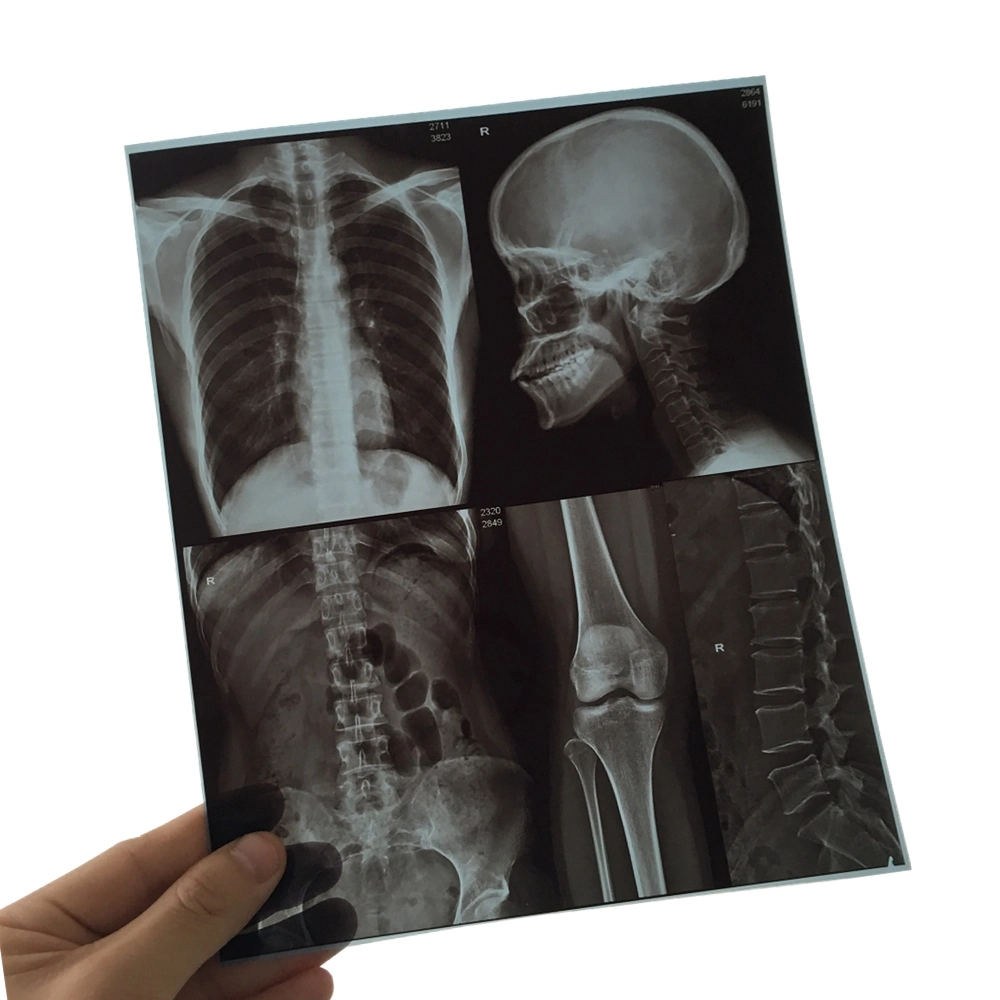

Application : Medical Image Digital Output

Compatibility : X Ray Machines

Function : Medical Diagnosis

Type : X Ray Film

11X14 Inch Medical X-ray Film/Analogue Medical Film/Dry Film Images |